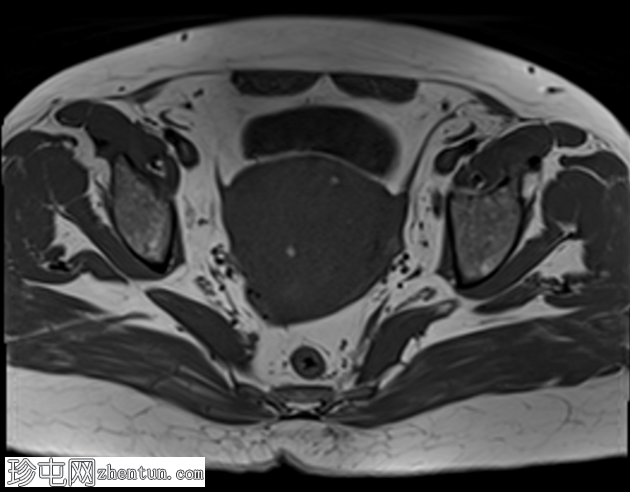

轴位

T2加权像

子宫增大,交界区弥漫性增厚,厚度约2.5 cm,边界模糊,在T1加权像和T2加权像上均可见无数点状高信号灶,提示出血灶。

在预期的膀胱尿道区域可见一小片异常信号强度的局灶性区域,T2加权像呈高信号,提示膀胱尿道子宫内膜异位症。

盆腔影像学检查(超声或MRI)通常显示局灶性或弥漫性、常不对称的子宫肌层增厚,并伴有异质性影像。

我们报告一例50岁女性患者,其超声和MRI影像均表现出弥漫性子宫腺肌症的特征性表现。